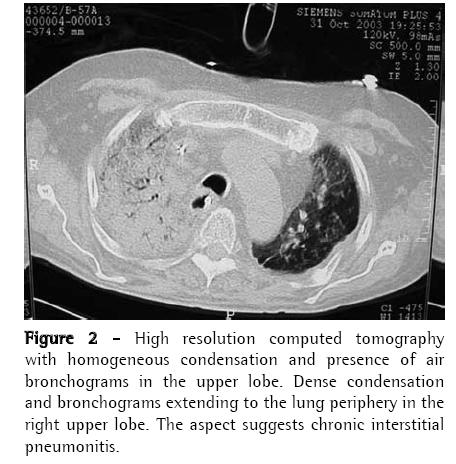

Case ReportA 56-year-old man diagnosed with IPF (using clinical, functional, tomographic and pathological criteria) five years prior, progressively evolved to dyspnea upon exertion and intense difficult-tocontrol cough with sparse mucoid expectoration. In the month preceding the lung transplantation, he presented hypoxemia and hypercapnia (arterial blood gas analysis with a PaO2 of 57 mmHg and arterial carbon dioxide tension of 45 mmHg at rest on room air at sea level), diffusing capacity of the lung for carbon monoxide at 29% of the predicted value, forced vital capacity of 40.8% (1.41 L), and forced expiratory volume in one second of 52.6% (1.31 L). Pulmonary perfusion scintigraphy revealed arterial flow of 76.7% for the right lung and 23.3% for the left lung. The laboratory tests for collagen-related diseases and the epidemiological investigation of known interstitial diseases were negative. During the five years of outpatient monitoring, the patient had been treated with corticosteroids (prednisone, 0.25 to 1 mg/kg/day), immunosuppressive agents (azathioprine or cyclophosphamide, 0.5 to 2 mg/kg/day), and an antifibrotic/immunomodulatory agent (interferon-γ1b) for four months. The transplantation was unilateral at left, corresponding to the minimal arterial perfusion and the greater intensity of the interstitial involvement according to the high-resolution computed tomography (HRCT) scan. Immediately after surgery, the patient evolved to thoracic instability due to the fracture of three ribs as a result of the osteopenic rib traction during the closure of the incision. He also presented ischemia of severe pulmonary reperfusion (arterial blood gas analysis with a PaO2/fraction of inspired oxygen ratio = 124). The patient was tracheostomized and remained on invasive mechanic ventilation (MV) for ten days, progressively recovering from hypoxemia. The immunosuppressive regimen began with 5 mg/kg of cyclosporine (12/12 h), 0.5 mg/kg/day of prednisone, and 2 mg/kg/day of azathioprine. In addition, anti-basiliximab interleukin-2 antibody was administered on postoperative days 1 and 4. Anti-methylprednisolone antibody (1 g) was also administered postoperatively. The patient was discharged from the intensive care unit to the semi-intensive care unit. However, on the eighth day in the semi-intensive care unit, he presented exacerbation of dyspnea, accompanied by the return of the dry cough and progressive crackling rales throughout the right hemithorax, and was therefore re-admitted to the intensive care unit. The patient was again submitted to an HRCT scan. In addition, fiberoptic bronchoscopy with bronchoalveolar lavage (BAL) was performed, together with transbronchial biopsy of the left lower lobe and the right upper lobe. All cultures tested negative, the BAL fluid presented a neutrophilic pattern, without eosinophils or hemosiderin-laden macrophages, and the histopathological analysis was inconclusive. A pulmonary arteriogram was performed, followed by thoracoscopic lung biopsy in three different regions of the right upper lobe to ensure that the disease was representative (Figures 1 and 2). The pulmonary arteriogram did not demonstrate thromboembolic disease. The biopsy culture was negative for bacteria, fungi, and mycobacteria. Herpes simplex virus and cytomegalovirus tests were also negative. Direct immunofluorescence for Chlamydia pneumoniae, Legionella pneumophila, and Mycoplasma pneumoniae, as well as for antigenuria for L. pneumophila serotype 1, were negative. The histological study of the biopsy of the three right lung areas showed an exclusive pattern of UIP, similar to the left native lung (Figure 3). Pulse therapy with 1 g of methylprednisolone was performed for three consecutive days. The patient remained on invasive MV, then evolved to sepsis caused by infection with Klebsiella pneumophila and Pseudomonas aeruginosa. On day 141 of the hospital stay, after the patient had been on invasive MV and using noradrenaline (0.2 µg/kg/day) for 109 days, transplant of the right native lung was carried out - bilateral sequential transplantation with more than a month interval - regardless of the relative contraindications: high dose of corticosteroid (>20 mg/day), MV, and sepsis treatment. (6)

According to data obtained from the International Society for Heart and Lung Transplantation,(2) more than 50% of the transplantations for IPF in 2006 were unilateral. Since unilateral transplantation involves directing ventilation and perfusion preferentially to the graft, IPF is an ideal disease model for this type of transplantation.(17) However, the native lung is a potential source of complications, including native lung 'cirrhosis' (chronic interstitial pneumonitis), which has yet to be reported in the literature.

The radiological imaging demonstrated condensation in the middle, upper, and lower right lobes, and the established diagnosis was IPF exacerbation in the native lung, mainly characterized by the UIP histological aspect (nonuniform and multifocal infiltrate, with inflammatory and fibrous thickening of the alveolar interstitium, pulmonary cysts, peribronchiolar fibrosis, alveolar hyperplasia, and absence of hyaline membranes), and the absence of microbial increase in lung tissues and cardiovascular decompensation. It is known that, in IPF, the lung becomes progressively collapsed, which can simulate images of pulmonary condensation. The accelerated variant of IPF has recently been described and should have its diagnosis characterized by ruling out other causes of exacerbation. The literature mentions, in unilateral lung transplantation, chronic progression of IPF in the native lung. However, there have been no reports of acute progression. This is the first case described in the national literature as IPF in its accelerated phase.